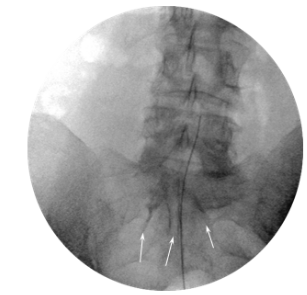

On the assumption of localization of the affected roots, we used classic caudal access to locate the introducer. From paramedian access, a puncture was performed in the hiatus sacralis; the Tuohy 16G introducer was placed at a level not higher than S3. The RCE electrode was moved through the introducer in the direction of the lumbar roots through the dorsal epidural space (Figure 1). There was no special protocol of fluid administration for hydrodissection or facilitating electrode conduction. The working tip of the electrode (15 mm) was located in the projection of the lateral canal opposite the exit zone and just dorsal to the affected nerve root, at the exact location of the determined nerve impairment or slightly proximal (Figure 2). After placement of the electrode, sensory stimulation was performed at 50 Hz, in the range of 0.3-0.5 V, and a typical sensation response was obtained that accurately overlapped the painful area of the patient. Because theventral and dorsal branches are very close in the impact zone, motor stimulation with 2 Hz was often also effective, but with a slightly higher voltage, most often within 1 V. Provided that the impedance in the impact zone corresponded to a normal value (200–400 Ohm), the PRF was started in monopolar mode with the following characteristics: frequency 2 Hz (20 ms pulse, 480 ms pause), amplitude 65V, exposure time 360 ​​sec, temperature in the action zone not exceeded 42 degrees Celsius. After the procedure, a water-soluble steroid was administered (dexamethasone, 8 mg) through the catheter (Figure 3). Patients remained in the hospital for at least 2 hours, upon expiration of the control period, and in the absence of warning signs, they were discharged home.

Figure  2 AP view. RCE electrode in lateral canal above the L5 nerve. Arrows – contrast material shown in the epidural space.